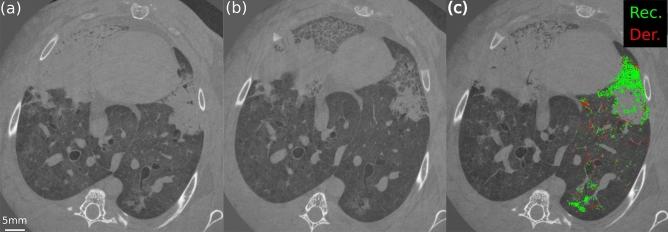

Mechanical ventilation can damage the lungs, a condition called Ventilator-Induced Lung Injury (VILI). However, the mechanisms leading to VILI at the microscopic scale remain poorly understood. Here we investigated the within-tidal dynamics of cyclic recruitment/derecruitment (R/D) using synchrotron radiation phase-contrast imaging (PCI), and the relation between R/D and cell infiltration, in a model of Acute Respiratory Distress Syndrome in 6 anaesthetized and mechanically ventilated New-Zealand White rabbits. Dynamic PCI was performed at 22.6 µm voxel size, under protective mechanical ventilation [tidal volume: 6 ml/kg; positive end-expiratory pressure (PEEP): 5 cmHO]. Videos and quantitative maps of within-tidal R/D showed that injury propagated outwards from non-aerated regions towards adjacent regions where cyclic R/D was present. R/D of peripheral airspaces was both pressure and time-dependent, occurring throughout the respiratory cycle with significant scatter of opening/closing pressures. There was a significant association between R/D and regional lung cellular infiltration (p = 0.04) suggesting that tidal R/D of the lung parenchyma may contribute to regional lung inflammation or capillary-alveolar barrier dysfunction and to the progression of lung injury. PEEP may not fully mitigate this phenomenon even at high levels. Ventilation strategies utilizing the time-dependence of R/D may be helpful in reducing R/D and associated injury.

机械通气可能会损伤肺部,这种情况被称为呼吸机诱导性肺损伤(VILI)。然而,导致 VILI 的微观机制仍知之甚少。在这里,我们使用同步辐射相衬成像(PCI)研究了急性呼吸窘迫综合征模型中周期性复张/复陷(R/D)的潮汐内动力学,以及 R/D 与细胞浸润之间的关系,该模型涉及 6 只麻醉和机械通气的新西兰白兔。在保护性机械通气下[潮气量:6ml/kg;呼气末正压(PEEP):5cmH2O]以 22.6μm 体素大小进行动态 PCI。在潮汐内 R/D 的视频和定量图谱中,发现损伤从非充气区域向外传播,向相邻存在周期性 R/D 的区域传播。周边气腔的 R/D 既与压力有关,也与时间有关,在整个呼吸周期内发生,开/闭压力的离散度很大。R/D 与局部肺细胞浸润之间存在显著相关性(p=0.04),这表明肺实质的潮汐性 R/D 可能导致局部肺炎症或毛细血管肺泡屏障功能障碍以及肺损伤的进展。即使在高水平时,PEEP 也可能无法完全减轻这种现象。利用 R/D 的时间依赖性的通气策略可能有助于减少 R/D 及其相关损伤。